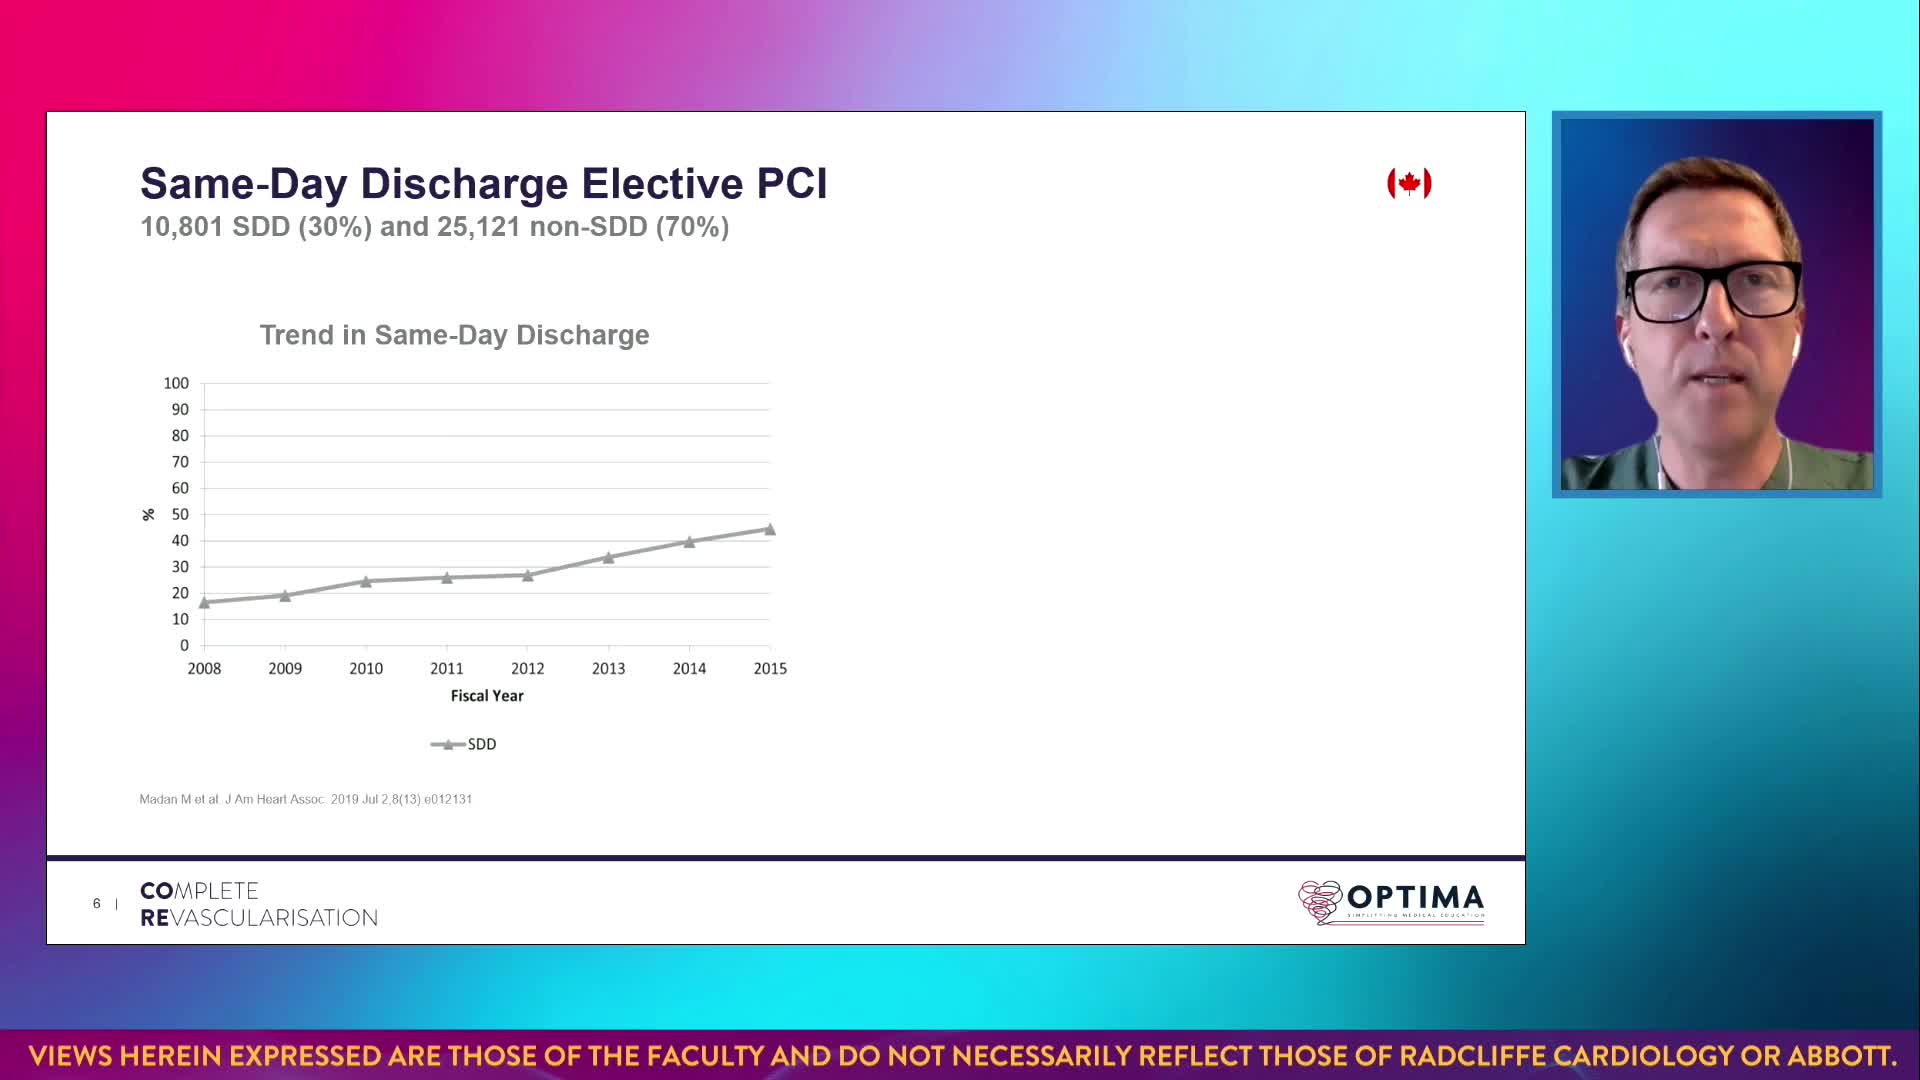

Session 2: Coronary calcium – too hard to crack?